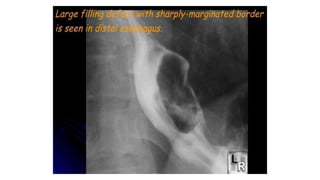

Submucosal or intramural mass.

Malignant mass at the distal esophagus.

Malignant mass atthe distal esophagus.